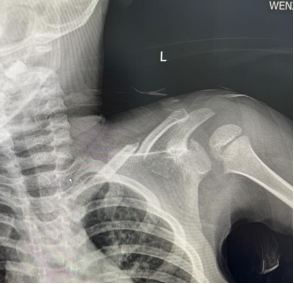

病例分享:

朱某,男,2016-3-15出生,因“跌倒致左肩疼痛伴活动受限2小时”2019年12月12日来我院门诊。检查发现左锁骨区见肿胀、畸形,明显压痛,左肩活动受限。本院X线摄片示:左锁骨骨折,断端明显重叠移位(图1),予以8字绷带外固定制动,定期随访。2020年1月17日复诊述左肩无肿痛,活动基本正常,摄片示:左锁骨骨折,断端对线欠佳,局部明显骨痂形成(图2)。2020年6月8日再次复查摄片示:左锁骨骨折,断端对线可,已骨性愈合(图3)。2023年9月26日再复查摄片示:左锁骨骨折部位已完成塑形,与健侧无明显差异(图4)。

图1